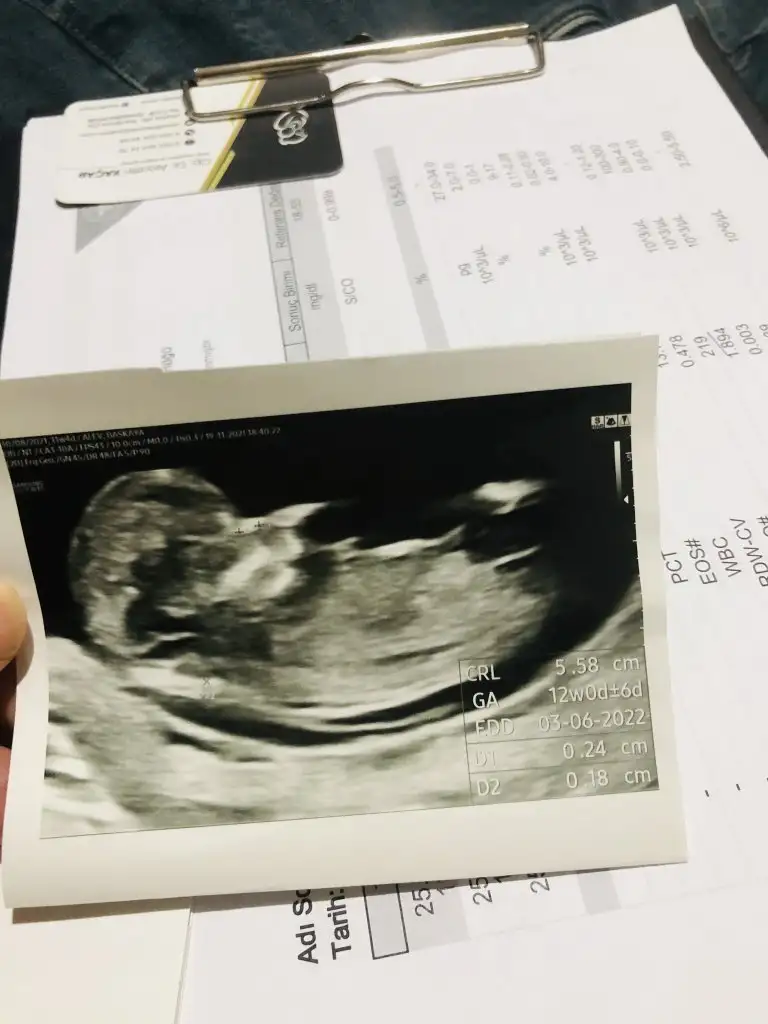

Belli belirsiz tam o bölge ama sanki kız gibi canım. Eki Görüntüle 2957287

Bana doktor zaten kız dedi.